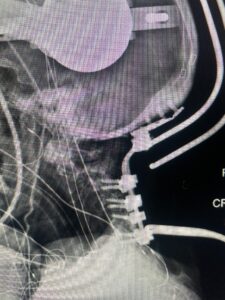

Fig 8: Intraoperative photograph demonstrating occipital-cervical construct and C1 laminectomy (blue dot). Note the 3 screws in the midline keel (blue arrow)

Cervical x-rays revealed a significantly increased atlanto-axial interval (Fig. 5) On review of her imaging studies it was noted that the right C2 isthmus was very thinned by the vertebral foramen (Figs 6a, b, and c) which would make an attempt at placing a C2 pars screw dangerous. A decision was made to perform an occipital-cervical fusion because only possible unilateral fixation and an extensive C1 laminectomy to be performed eliminating a fixation point if a more traditional C1-C2 was performed. Even if C1 lateral mass screws were able to be placed one could only perform a unilateral screw construct fixation to C2. We performed an occipital cervical fusion down to C4 to get enough inferior fixation and C1 laminectomy. The decompression went well. We placed a left unilateral pars screw and bilateral C3 and C4 lateral mass screws. We placed three 12 mm screws in the midline keel (Fig. 7). Postoperatively the patient had all around improvement in her symptoms and did not qualify for rehab. Her post op films at 6 weeks (Fig. 8)

Fig. 8: Intraoperative photograph demonstrating occipital-cervical construct and C1 laminectomy (blue dot). Note the 3 screws in the midline keel (blue arrow)